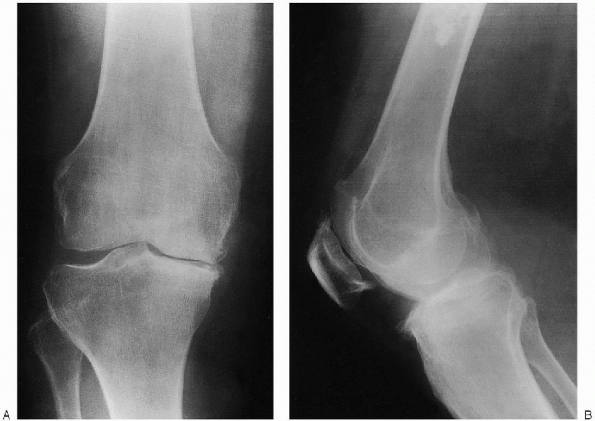

![]() |

FIGURE 27-2. Preoperative weight-bearing radiographs demonstrate varus osteoarthritis: anteroposterior view (A) and lateral view (B).

overstated in the case of upper tibial osteotomy. The exact angular

correction must be determined with the use of a long leg alignment film

series. The potential distortion attributable to fixed contractures must be eliminated through the use of weight-bearing views (Fig. 27-2). This

minimizes the risk of overcorrection if the joint space asymmetry is

amplified by spurious opening of the lateral space from a medial joint

contracture in an unloaded situation. The goal of the procedure

is to restore the valgus alignment of the leg. Numerous studies have

demonstrated that one of the most reliable prognostic factors is a

correction to a valgus alignment of at least 8 degrees of valgus. This

implies a transfer of the mechanical axis to a point within the

innermost portion of the lateral third of the joint line on the coronal

anteroposterior projection.